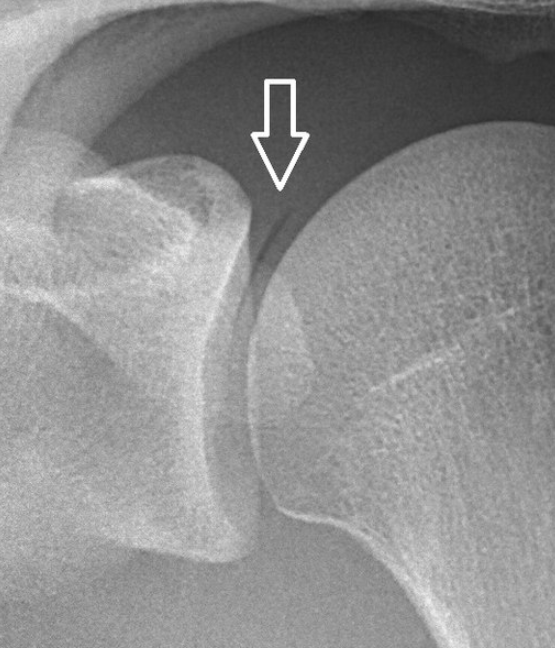

오십견은

중년 이후에 많이 나타나는 질병으로 어깨 통증이나 어깨 관절의 움직임 제한을

통칭해서 부르는 말로 의학용어로는 ‘유착성 관절낭염’이라 하고

'동결견'이라고도 합니다.

주로 50대 이후에 발병하는 질환이라 하여 붙여진 이름으로

어깨 관절을 감싸고 있는 관절낭에 만성 염증이 원인이 되며,

최근에는 연령 제한 없이 젊은 나이에도 많이 나타나는 증상입니다.